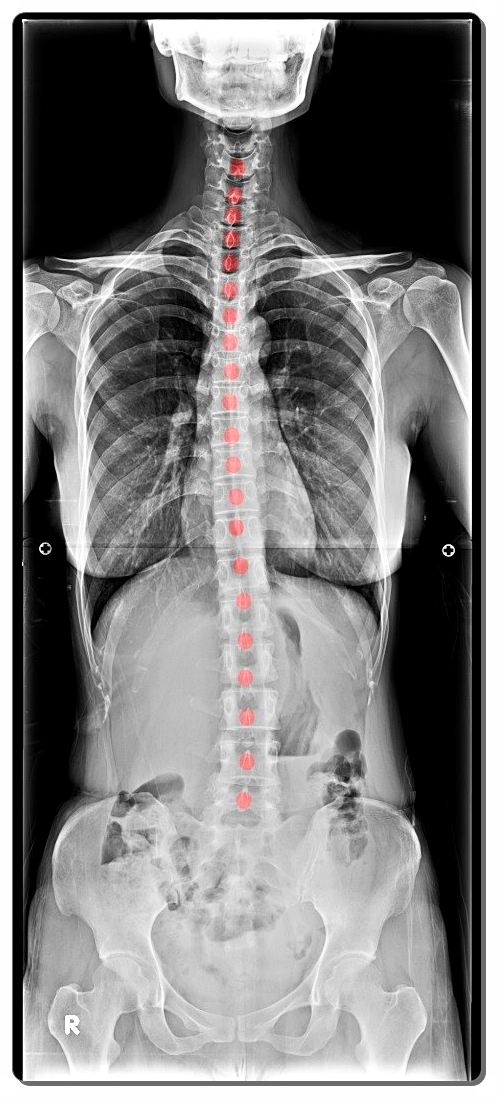

척추측만증은 쉽게 말하면 척추가 옆으로 휘어지는 질환입니다.

하지만 겉모습의 문제만이 아니라, 근육의 비대칭적 긴장과 신경 자극의 불균형이 함께 나타나는 기능적 질환이기도 합니다.

예를 들어 오른쪽 허리 근육이 짧아지고 왼쪽이 과도하게 늘어나면, 척추는 중심을 맞추기 위해 스스로 비틀립니다.